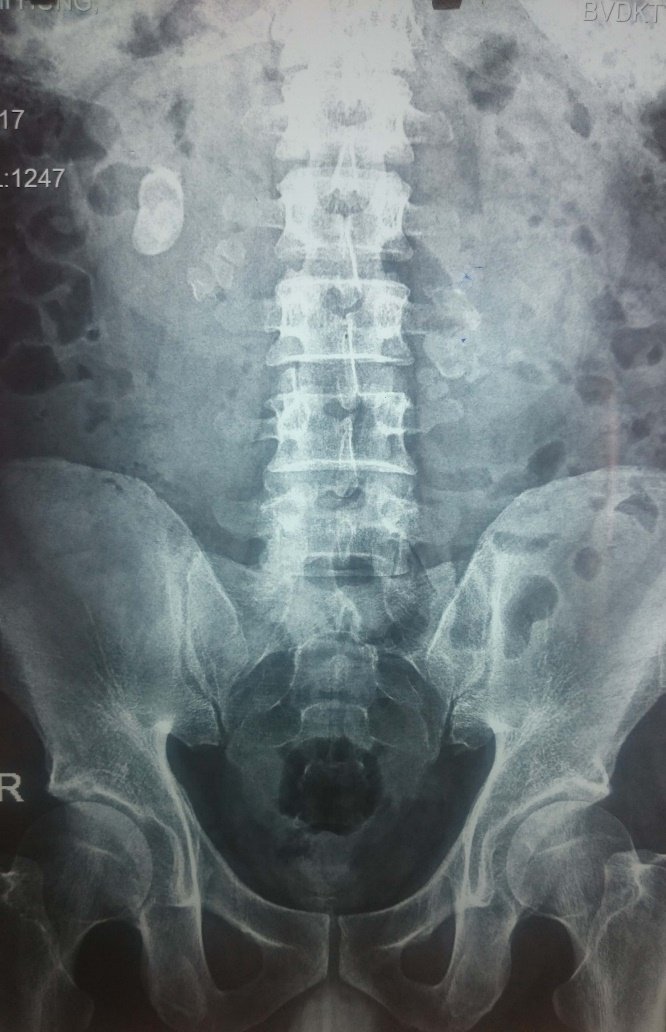

Chụp X-quang hệ tiết niệu có thể phát hiện sỏi cản quang. Nên áp dụng phương pháp này cho bệnh nhân đã có tiền sử sỏi cản quang; không chỉ định cho bệnh nhân nữ có thai, bệnh nhân ở độ tuổi sinh đẻ cần làm test thai trước khi chụp. Đối với các đối tượng này, tốt nhất là nên làm siêu âm tiết niệu.

- Chụp bụng hệ tiết niệu, siêu âm hệ tiết niệu hoặc chụp CT không cản quang hệ tiết niệu có sỏi niệu quản.